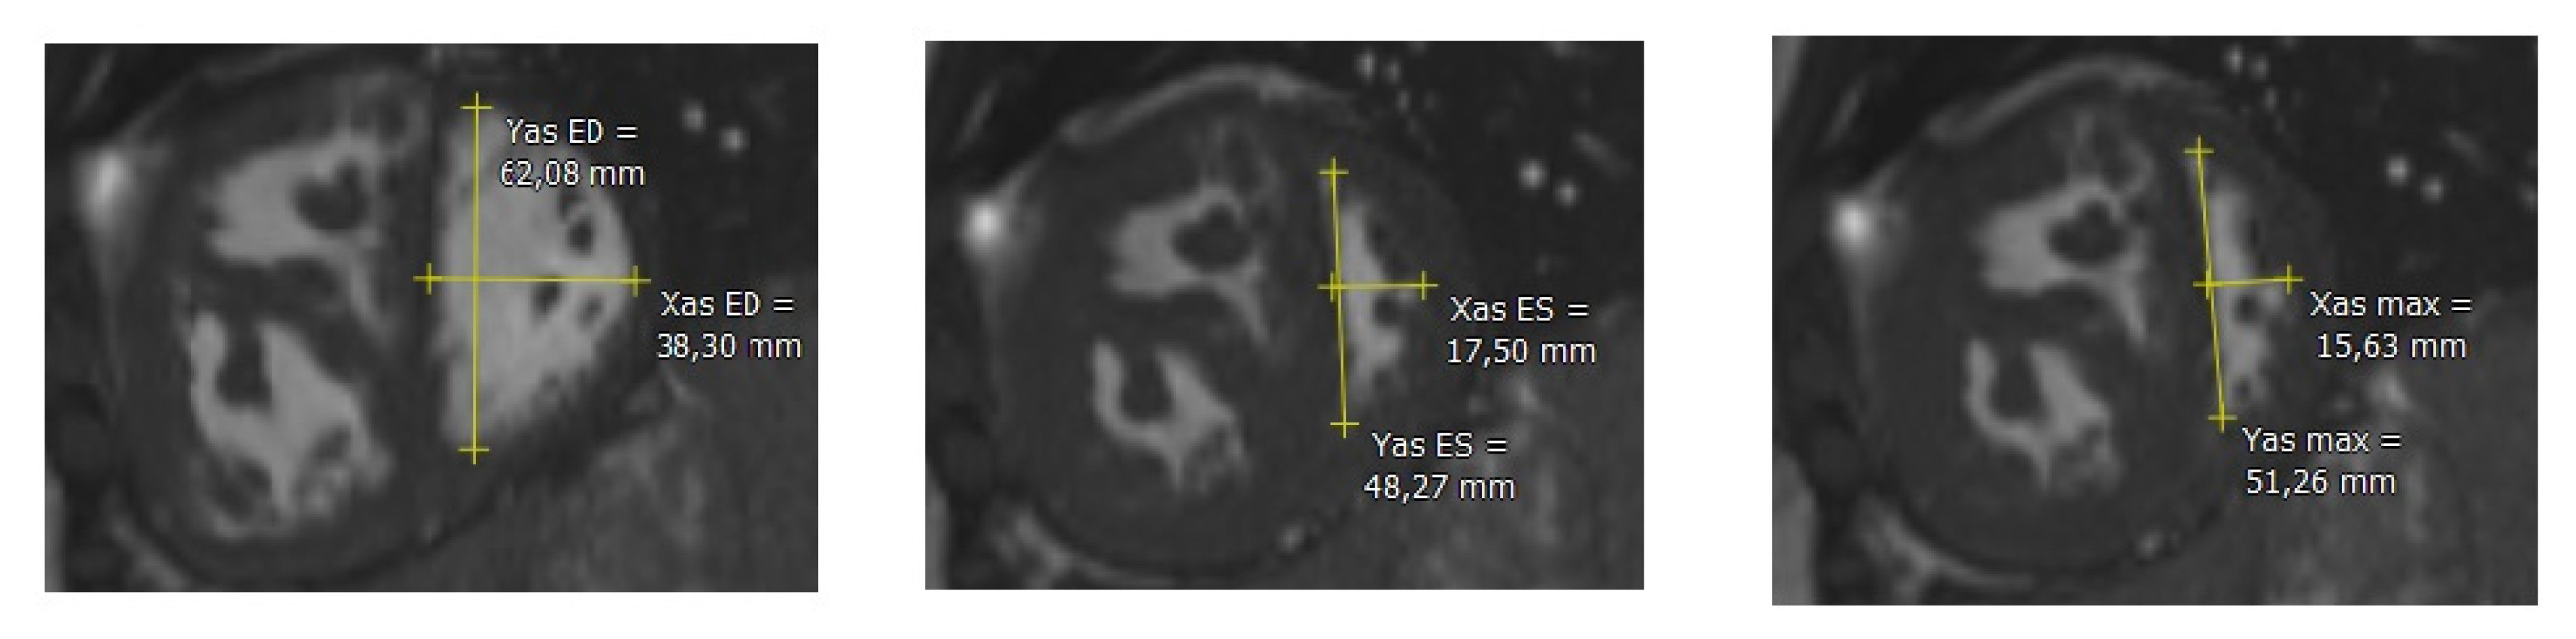

2.2. Cardiac Magnetic Resonance

2.3. Post-Processing